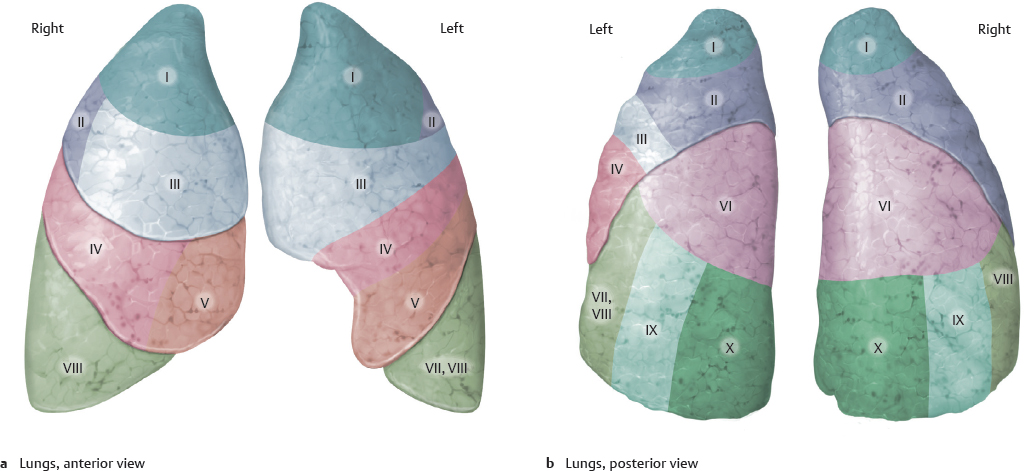

Анатомические изображения сегментов легких различных животных

Раздел: Другие животные